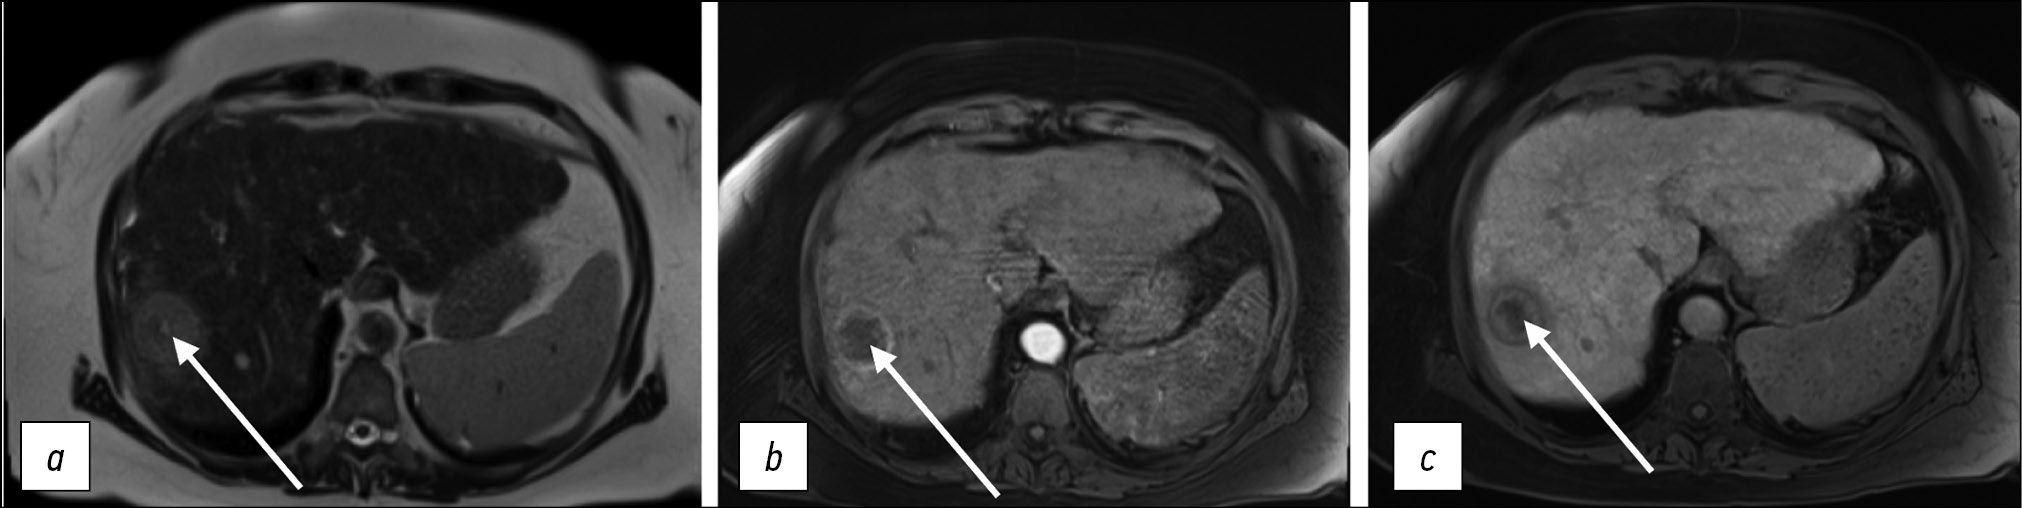

DWIs are widely used in abdominal radiology. The most common are single-shot echoplanar sequences with or without breath-holding. Parallel data acquisition is used to reduce scan time and more accurately calculate the apparent diffusion coefficient, and modern techniques allow for taking DWIs with high spatial resolution in <1 min (simultaneous multislice imaging DWI) [16] (Fig. 9).

Figure 9. Comparison of standard (STD DWI) and simultaneous (SMS DWI) multislice diffusion-weighted images with free breathing and respiratory triggering using various b-factors (50, 400, and 800 s/mm2) and corresponding apparent diffusion coefficients. The mean scan time was 10:30 min (5:56–18:13) for STD DWIs and 3:29 min (2:19–4:27) for SMS-DWIs [16].